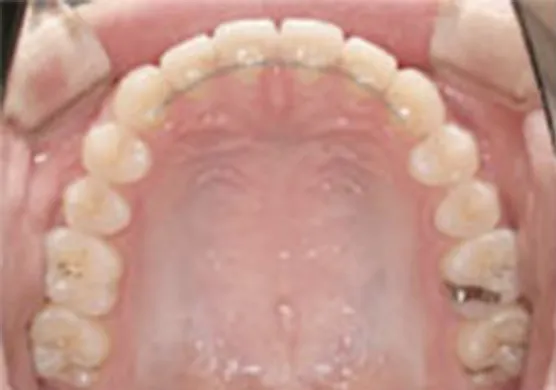

全体矯正・1期治療後の全体矯正

(2期治療)全ての歯に矯正装置を付けて、機能的・審美的要素を考慮して矯正治療を行ないます。精密に歯並びを整えるため1本1本の歯を移動し、噛み合わせを改善するのが目的です。